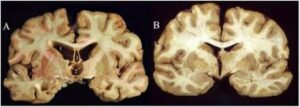

I’m sure you heard about the 27-year-old man who drove from Nevada to NYC last week, entered what he thought was the headquarters of the NFL, and killed four people and critically injured a fifth before offing himself. “Luckily,” he left a note of explanation: He believed he had chronic traumatic encephalopathy (CTE), a degenerative brain disease linked to repeated head trauma, which causes symptoms including memory loss, confusion, and aggression.

The disease is common in football, with 99% of donated NFL player brains indicating CTE.